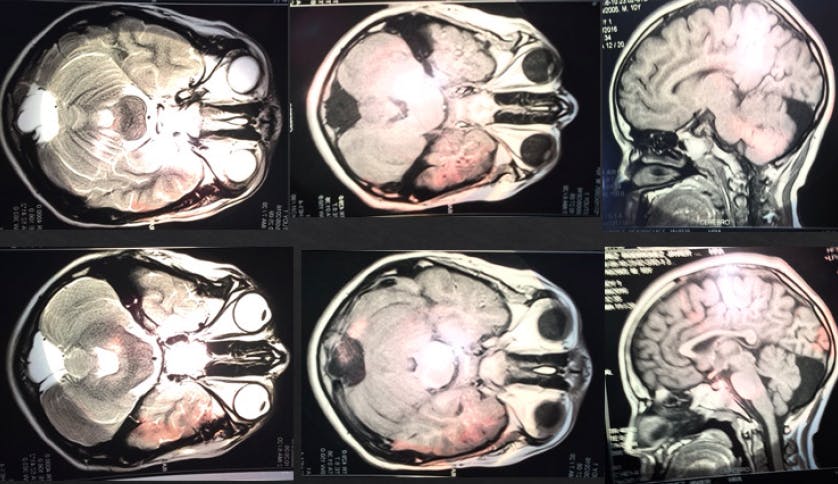

At 8 years, a fundoscopic examination revealed pallor of the patient’s optic disc, vascular attenuation, and a diffuse grainy appearance of the retinal pigment in the periphery in both eyes (Figure 1). Electroretinography (ERG) revealed bilateral low amplitude for waves A, B, and C under scotopic conditions, suggestive of severe pigmentary retinopathy.

<p>Figure 1. Fundoscopy at presentation showed pallor of the optic disc, vascular attenuation, and a diffuse grainy appearance of pigment in the retinal periphery.</p>

Figure 1. Fundoscopy at presentation showed pallor of the optic disc, vascular attenuation, and a diffuse grainy appearance of pigment in the retinal periphery.

MRI showed the presence of a mega cisterna magna (Figure 2). Family history revealed that the patient's younger sister had experienced visual decline 1 year prior, and another boy with a similar last name in the same village had also presented with similar symptoms.

<p>Figure 2. Head MRI showed the presence of mega cisterna magna.</p>

Figure 2. Head MRI showed the presence of mega cisterna magna.

Neurologic examinations are usually abnormal, as 75% of JNCL patients develop disorders such as cognitive impairment, change in mood or behavior, and gait disturbances.3,5 The main neuroimaging findings are cerebral atrophy, cerebellar atrophy, and periventricular and thalamic signal changes.6 In this patient, MRI showed the presence of a cerebellar cyst.